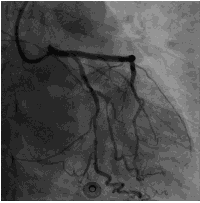

造影结果2: 左主干正常,前降支弥漫性斑块,近中段80%~90%狭窄,回旋支中远段80%~90%狭窄。

![]()

造影结论及应对策略:本病例行冠脉造影发现: 右冠弥漫性病变,近中段90%狭窄。左主干正常,前降支弥漫性斑块,近中段80%~90%狭窄,回旋支中远段80%~90%狭窄。家属要求PCI治疗。本次先开通右冠,择期开通左冠。